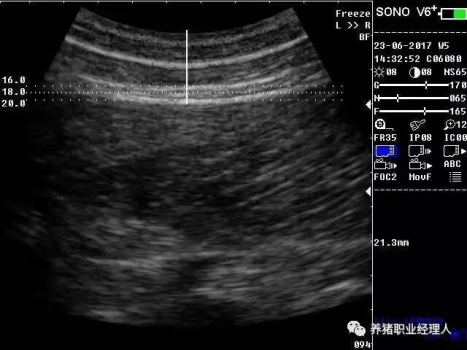

根據(jù)以上表格,活體測(cè)膘與實(shí)體測(cè)膘的相關(guān)分析及活體膘厚與胴體瘦肉率的相關(guān)分析結(jié)果證明,最后肋骨處和腰薦結(jié)合處離背中線5cm處(B5、C5)可作為活體測(cè)膘的最佳部位。 根據(jù)中華人民共和國(guó)農(nóng)業(yè)行業(yè)標(biāo)準(zhǔn)(NY/822-2004)種豬生產(chǎn)性能測(cè)定規(guī)程規(guī)定:生產(chǎn)性能背膘值運(yùn)用A超儀器測(cè)量的需測(cè)定腰薦椎結(jié)合處(P1)、胸腰椎結(jié)合處(P2)距背中線左側(cè)5cm處,兩點(diǎn)背膘厚平均值。生產(chǎn)性能背膘值運(yùn)用B超儀器測(cè)量的需測(cè)定倒數(shù)第三和第四肋骨間距背中線左側(cè)5cm處背膘厚。 2.3 剔剪剪毛 因?yàn)槌暡ㄊ遣荒茉诳諝庵袀鞑サ?,所以在利用儀器測(cè)量之前,先用剔剪剪去測(cè)定部位的豬毛,方便測(cè)量?jī)x器探頭與豬皮膚的無(wú)縫接觸。剪毛面積一般為5cm×5cm左右。此時(shí)若皮膚死皮結(jié)痂較多,便可用溫水擦洗去痂。 2.4涂耦合劑 耦合劑是檢測(cè)儀探頭與豬皮膚之間的中間潤(rùn)滑劑,作為超聲波從儀器發(fā)出到豬體表和從豬體表回到儀器的傳播介質(zhì)。所以耦合劑的作用是排除探頭與豬體表之間的空氣和作為超聲波傳播的介質(zhì)。它是準(zhǔn)確測(cè)定背膘所不能缺少的。 2.5 正確測(cè)量 因?yàn)樨i體表脂肪分為三層。所以不管是用A超還是B超,我們一般都能同時(shí)測(cè)量到三個(gè)數(shù)值,而正確反映豬只體況的是第三個(gè)數(shù)值。如圖所示:

測(cè)量時(shí),盡量讓豬只安靜,避免豬只弓背或塌腰而使測(cè)量數(shù)據(jù)出現(xiàn)偏差。探頭應(yīng)直線平面與豬背正中線縱軸面垂直,不可斜切。同時(shí)探頭應(yīng)與豬背密接且不重壓。 2.6 讀取記錄數(shù)據(jù) 若為A超,讀取儀器亮三個(gè)指示燈時(shí)的數(shù)值,記錄下來(lái)。若為B超,觀察并調(diào)節(jié)屏幕影響,獲得理想影像時(shí)即凍結(jié)影像,測(cè)量背膘厚和眼肌面積,并加以說(shuō)明標(biāo)記。影響打印或保存處理。 3、通過(guò)背膘測(cè)定指導(dǎo)豬生產(chǎn)飼喂管理 以妊娠母豬為例: 表3 妊娠母豬適宜背膘值范圍